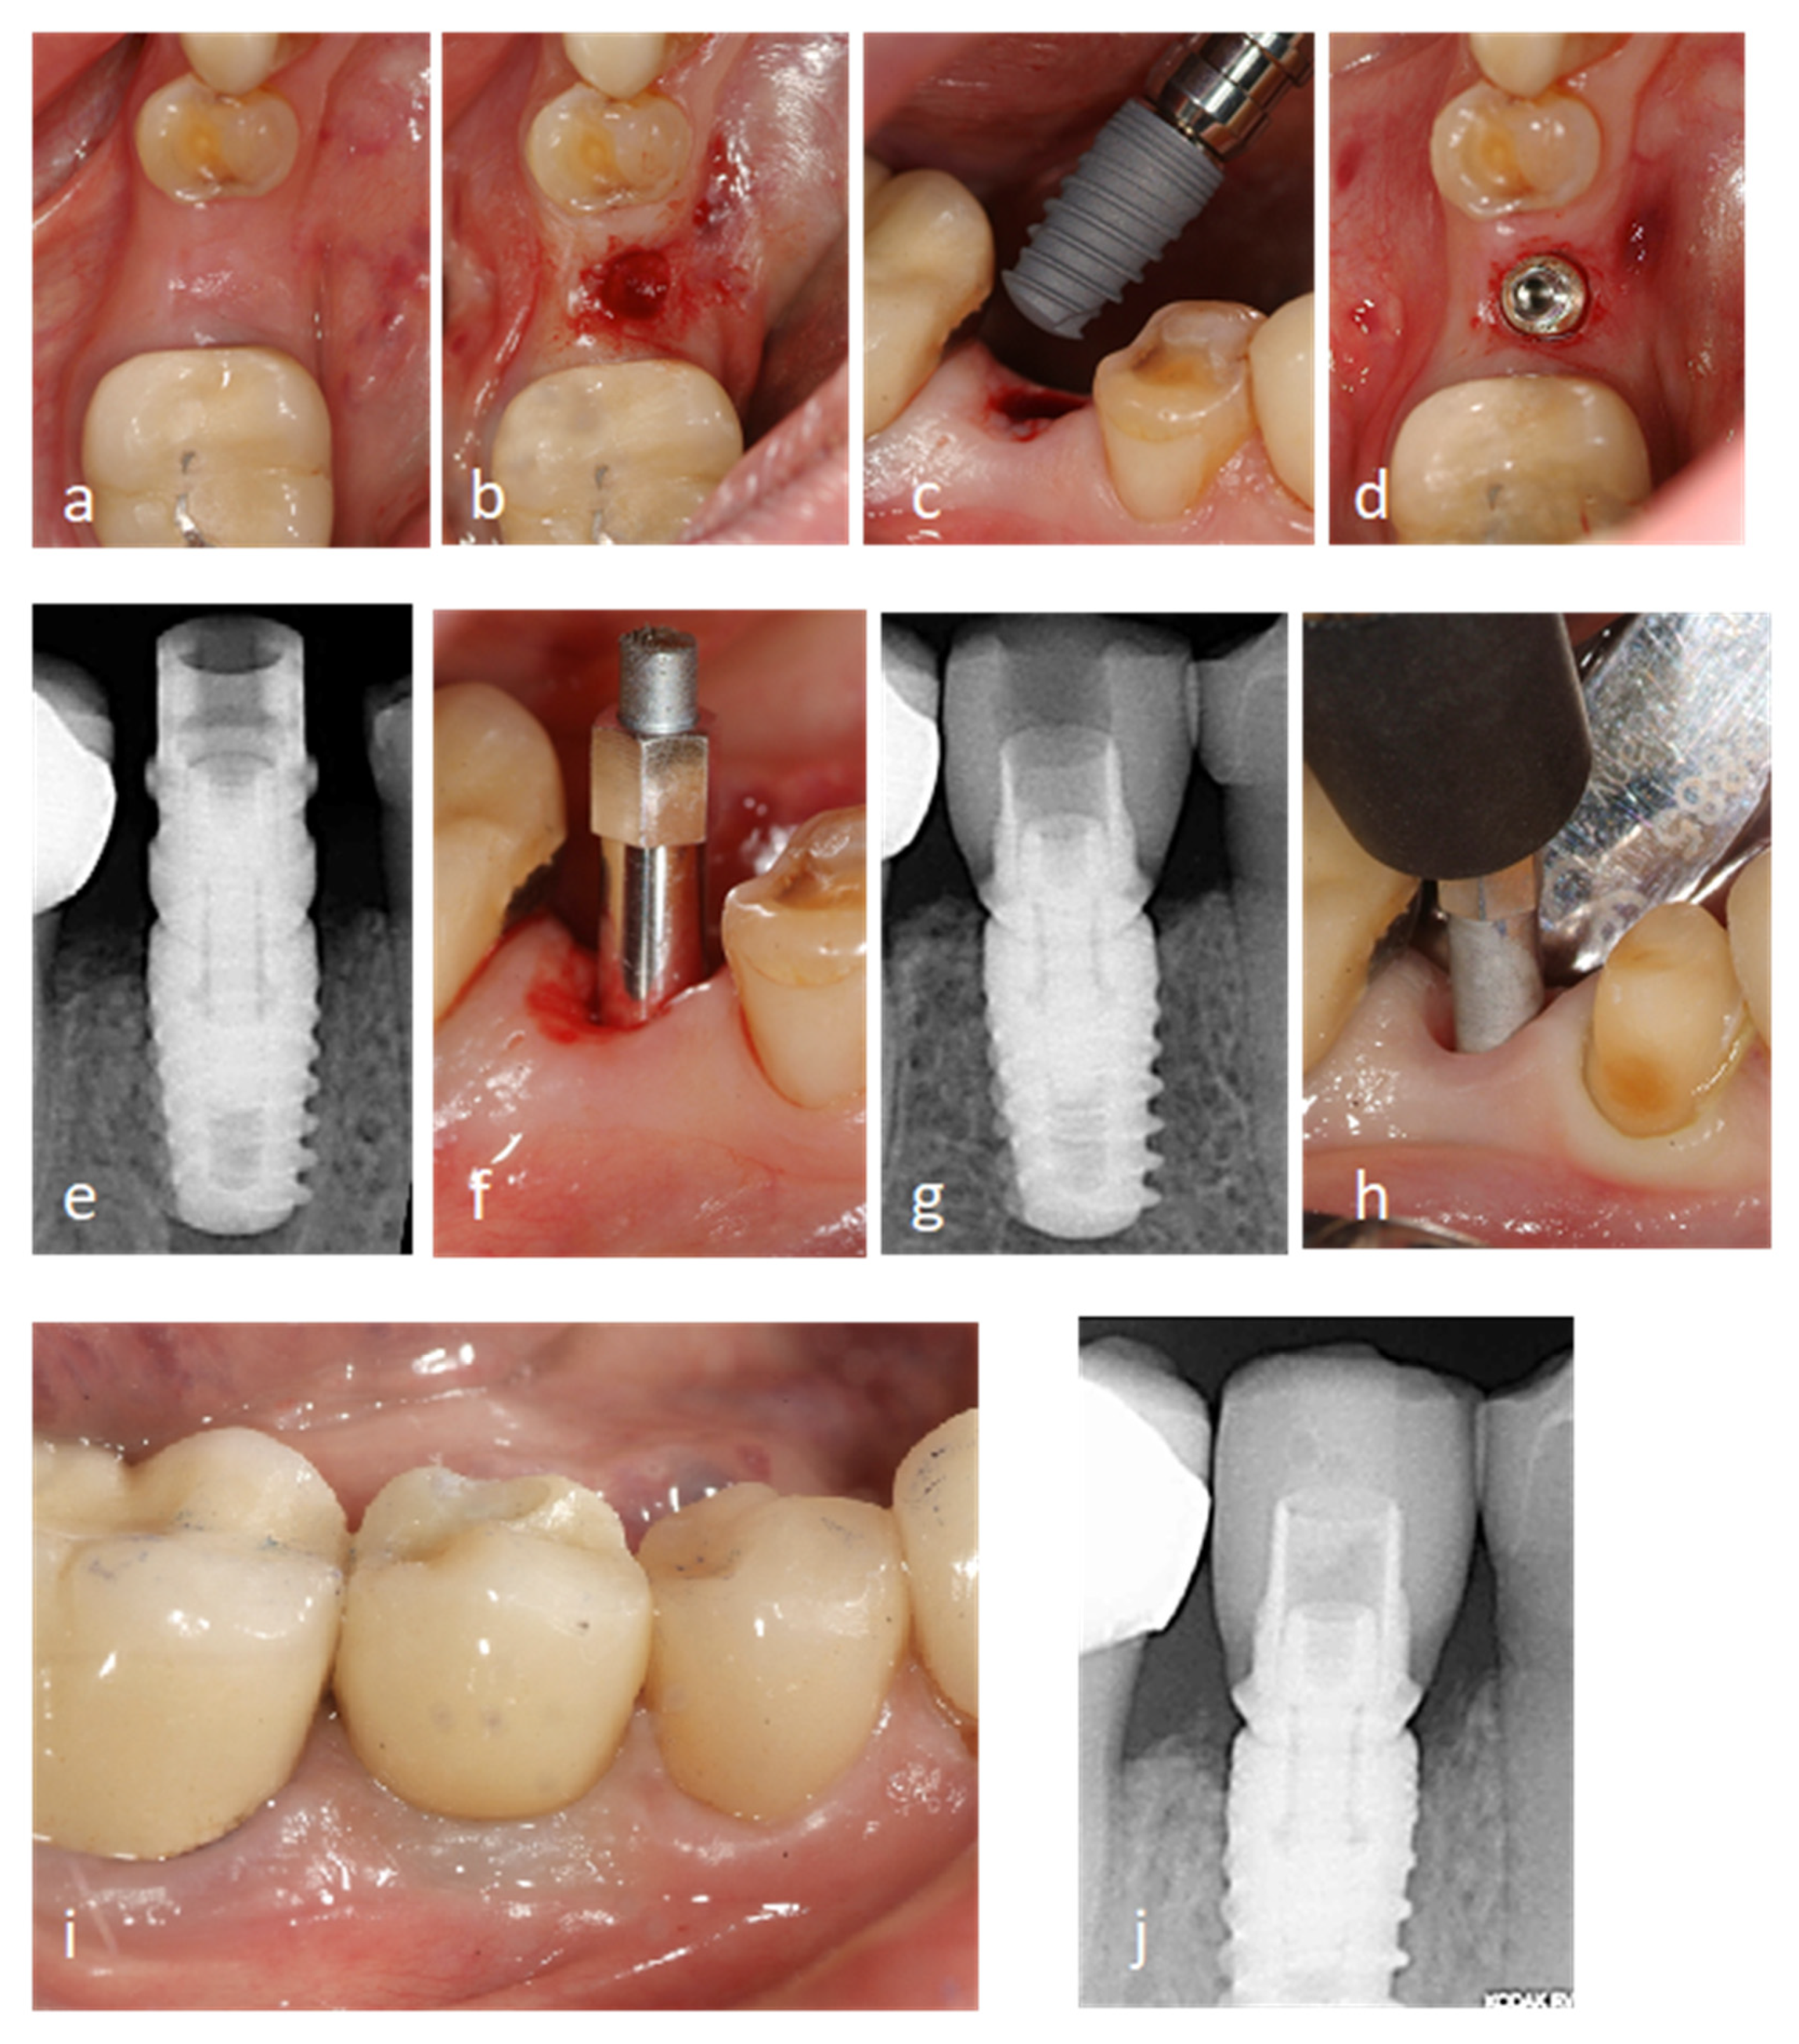

2.2.1. Surgical Procedure

2.2.2. Prosthetic Procedure